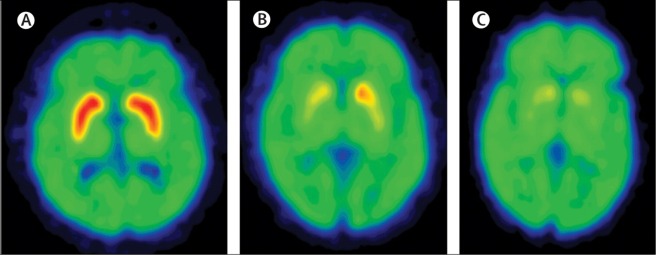

People with Parkinson’s disease will often be tested with a brain scan called a DAT-scan when they are diagnosed. This imaging technique results assesses the amount of dopamine being released in the putamen. It results in a horizontal image of the brain being presented on a computer screen with red (hot) regions that overlap with the location of the putamen in healthy individuals, indicating the normal release of dopamine. In people with Parkinson’s disease, however, there is a significant reduction in the release of dopamine (due to less dopamine neurons being present to generate dopamine), resulting in less red colouring on the computer screen image of the brain. In people with later stage Parkinson’s disease, there is even less colouring on the computer image (see image below).

Dopamine transporter (DAT) in normal (A), early Parkinson’s (B) and late stage Parkinsons’ (C) brains. Source: Lancet